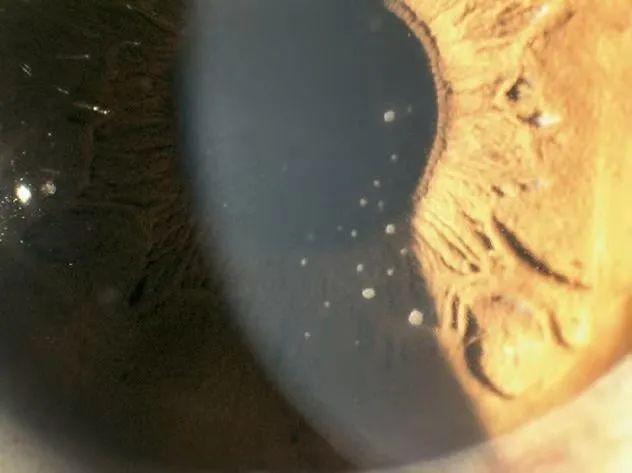

小洁右眼眼压高达55mmHg(正常眼压是10-21mmhg),右眼球结膜轻度充血,角膜上皮雾状水肿,角膜后下方见数枚羊脂状沉着物,确诊为青光眼睫状体炎综合征。

角膜后下方见数枚羊脂状沉着物